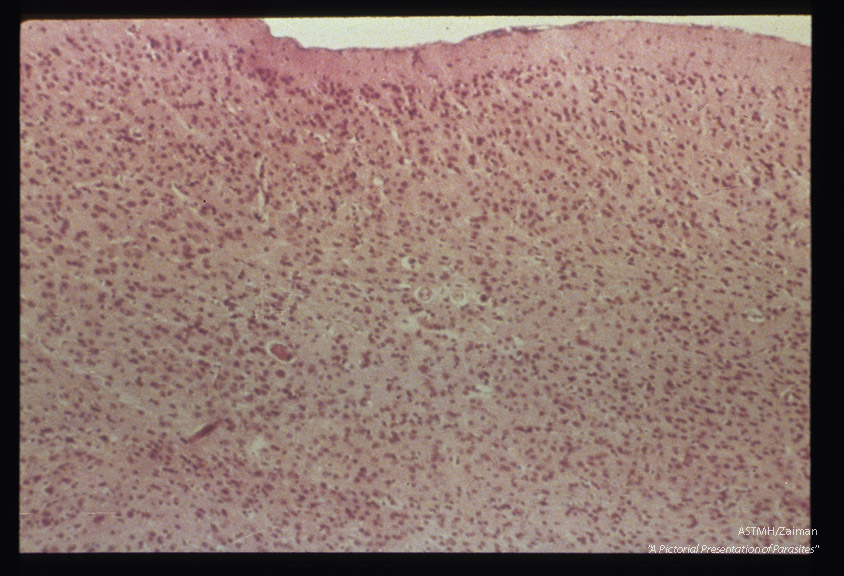

Hematoxylin-eosin stained sections of infected mouse brain.

Toxocara canis

Description: Hematoxylin-eosin stained sections of infected mouse brain.